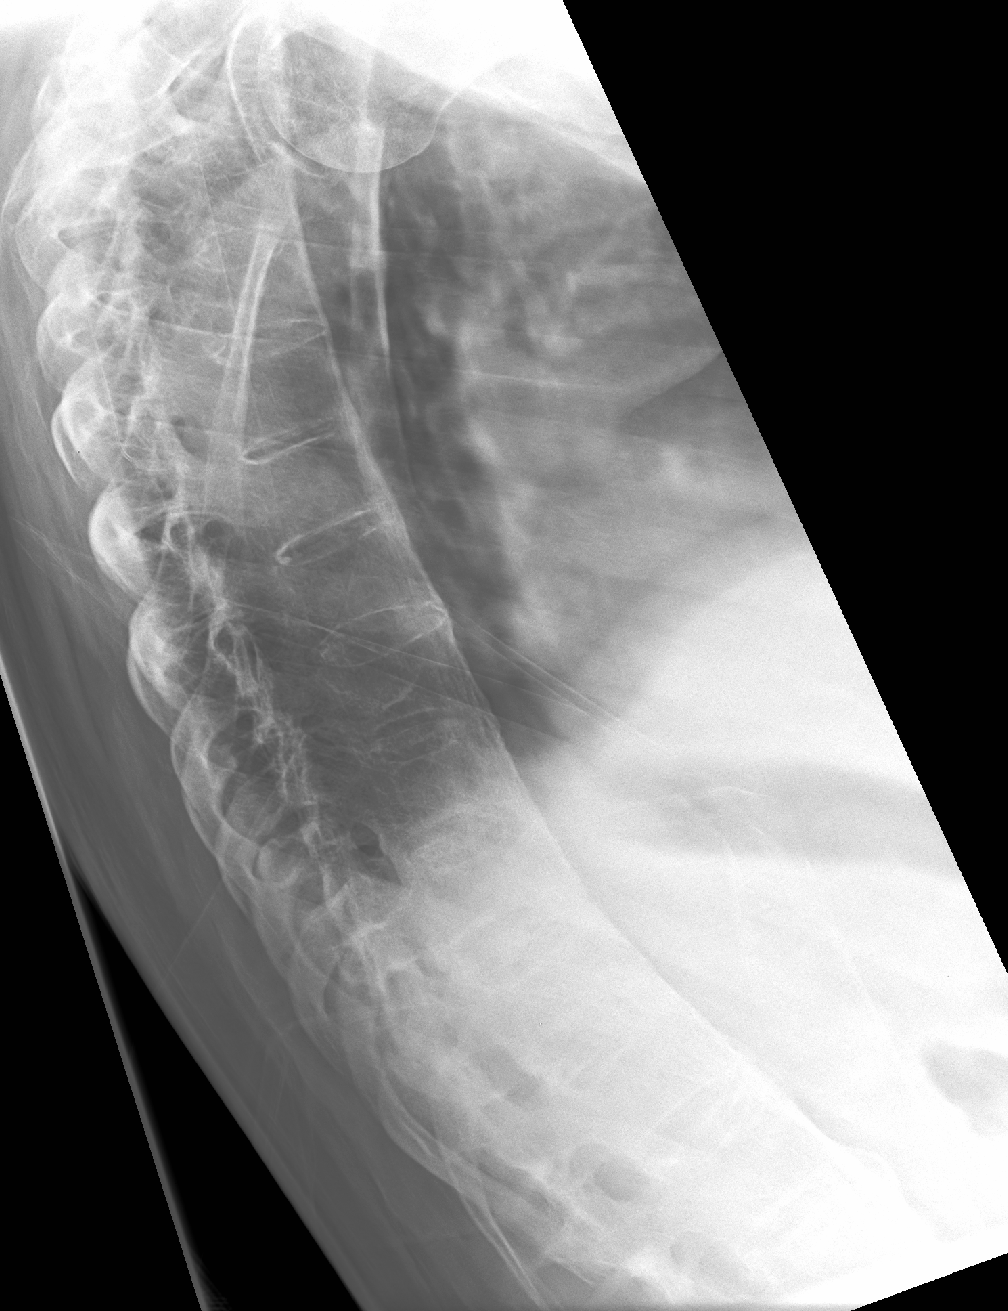

"대나무 척추"는 섬유륜(''anulus fibrosus disci intervertebralis'')의 바깥 섬유가 골화될 때 발생하며, 이는 인접한 척추 사이에 변연 신데스모파이트가 형성되는 결과를 초래한다.

단순 X-ray에서 가장 초기에 나타나는 변화는 천장관절의 침식과 경화이다.[23] 침식이 진행되면 관절 공간이 넓어지고 뼈가 경화된다. X-ray 척추 사진은 신데스모파이트라고 하는 뼈 가시 형성으로 척추가 사각형이 되는 것을 보여줄 수 있으며, 이는 대나무 척추 모양을 유발한다. X-ray 진단의 단점은 강직성 척추염의 징후와 증상이 일반적으로 단순 X-ray에서 확인 가능한 변화가 나타나기 7~10년 전에 이미 나타난다는 것이다. 이는 적절한 치료법을 도입하기 전에 최대 10년의 지연이 발생할 수 있음을 의미한다.[23]

질병이 진행됨에 따라 척추와 요천추 관절이 골화되어 척추가 유합될 수 있다.[44] 이로 인해 척추는 하나의 뼈가 되어 운동 범위가 줄어들 뿐만 아니라 척추 골절의 위험이 높아진다. 척추가 완전히 유합되면 운동 범위가 감소하고 통증이 증가하며, 관절이 완전히 파괴되어 관절 치환술이 필요할 수 있다.[45]

골다공증은 강직성 척추염 환자에게 흔하며, 만성적인 전신 염증과 운동 능력 감소가 원인이다. 장기간에 걸쳐 척추의 골감소증 또는 골다공증이 발생하여 압박 골절과 등의 "혹"을 유발할 수 있다.[46] 척추 후만증은 이동성과 균형 장애를 유발하고, 주변 시야를 손상시켜 낙상 위험을 증가시킨다.[46] 진행된 강직성 척추염의 전형적인 징후는 X-레이에서 신데스모파이트 형성 및 골극과 유사한 비정상적인 뼈 성장이다. 척추 압박 골절에서는 신경 주변 조직 염증으로 인해 감각 이상이 나타나기도 한다.